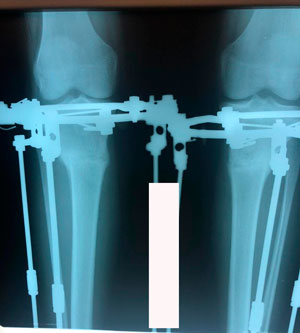

Дата операции - 20.03.2020

Дата снятия аппаратов - 11.06.2020

Срок сращения - 83 дня.